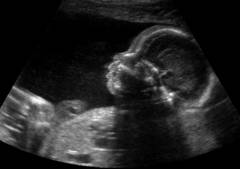

Гидроцефалию у ребенка чаще всего выявляют во время планового УЗИ, когда он еще в утробе. На экране видны расширенные желудочки головного мозга и скопление жидкости. Иногда размеры головы начинают увеличиваться до рождения, что может затруднить роды.

Гидроцефалия у детей чаще всего диагностируется во время ультразвукового исследования в утробе матери. На экране видно увеличенные желудочки головного мозга с накопленной жидкостью. В некоторых случаях размеры головы начинают увеличиваться до рождения, что может усложнить роды.